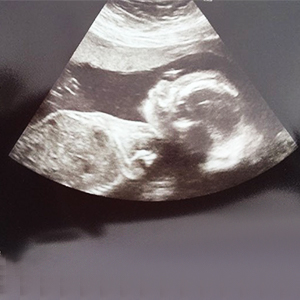

Early pregnancy ultrasound

An ultrasound is a painless diagnostic test that relies on sound waves, and most women will have at least one during pregnancy. Your first ultrasound will typically be done between 18 and 20 weeks, but you may have one before 12 weeks to confirm your due date.